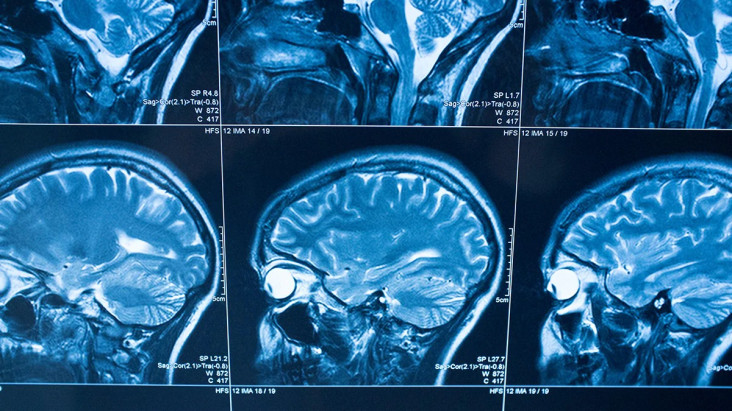

Layanan pre-hospital adalah langkah krusial pada penanganan stroke oleh sebab itu stroke memerlukan intervensi medis di “golden period”, yaitu waktu emas 4.5 jam dari sejak stroke terjadi. Tindakan cepat lalu tepat pada penanganan stroke dapat meminimalkan kecacatan otak, mengempiskan kecacatan, hingga menghindarkan pasien dari kematian.